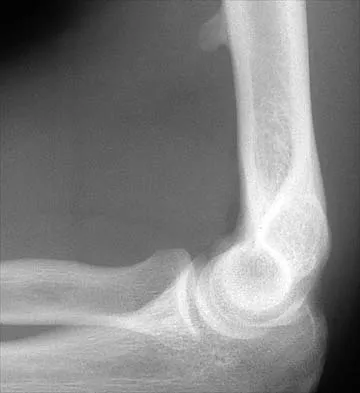

Figure 12 shows a lateral radiograph of the elbow. What is the most likely diagnosis?